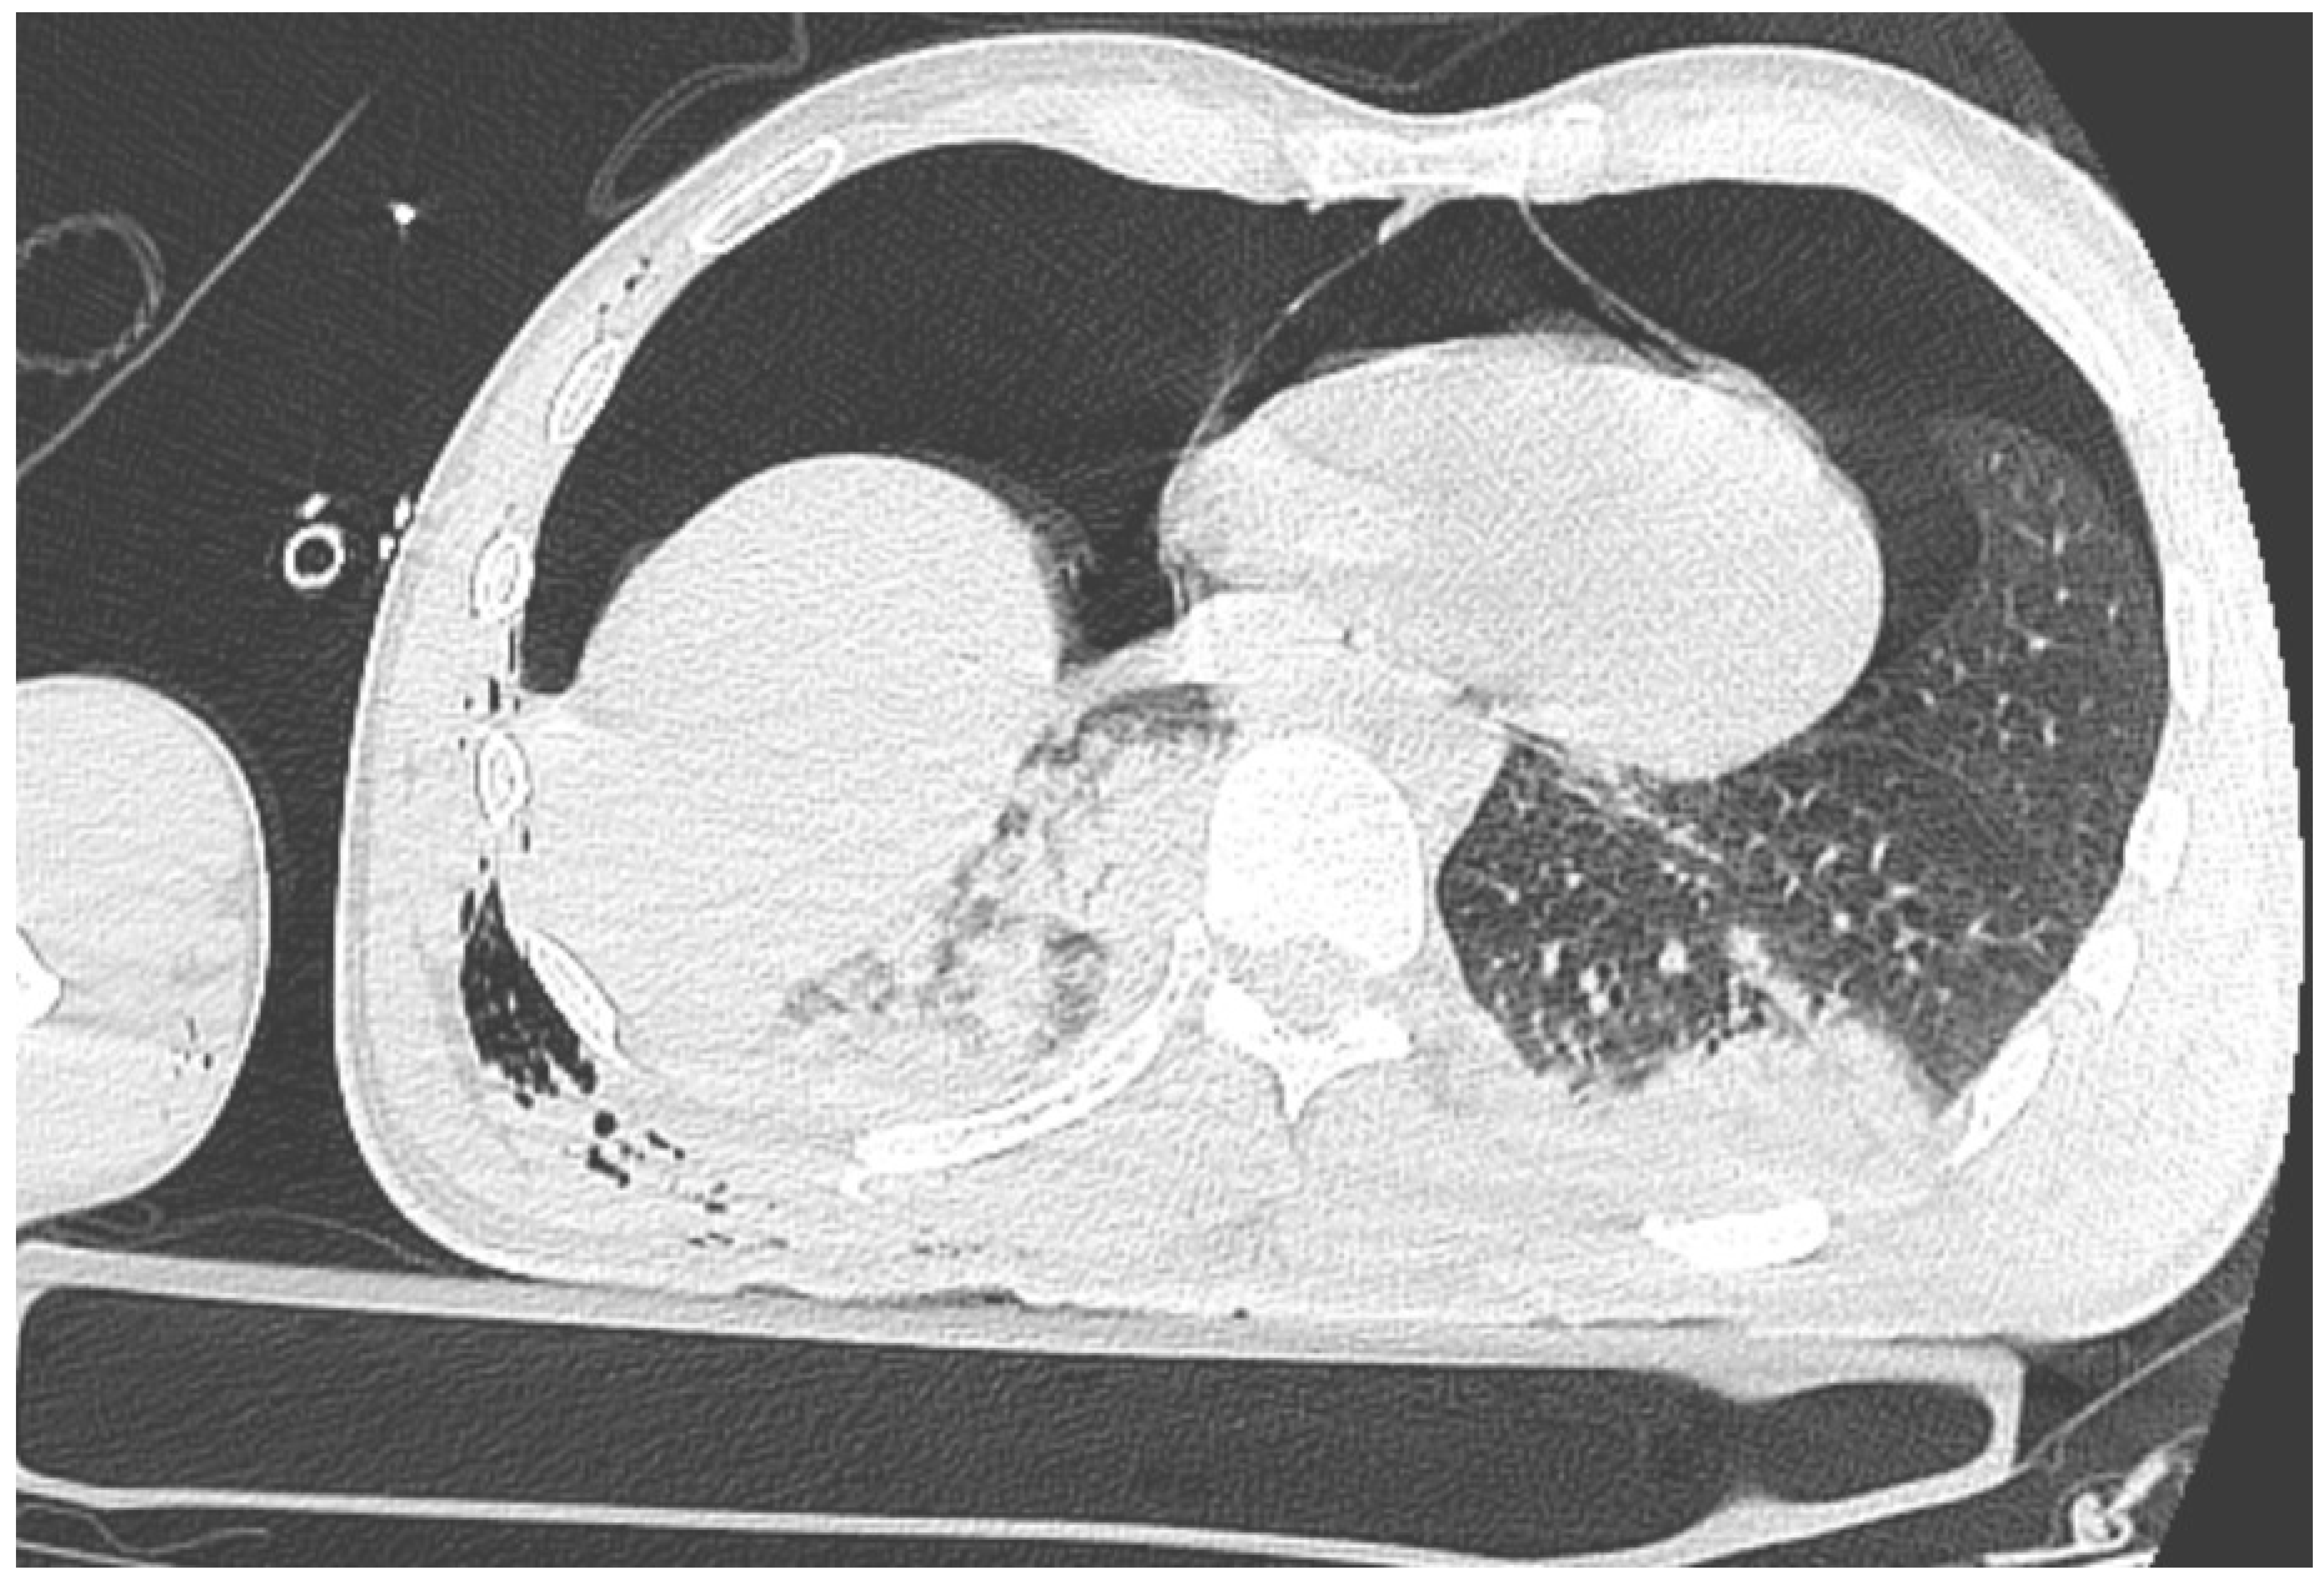

A CT (Computed Tomography) scan showed right-sided pneumothorax with a chest drain (the maximum width of pneumothorax 20 mm) and a pneumopericardium (max. 30 mm) with the symptoms of compression of the anterior wall of the heart. There were features of cardiac tamponade (Figure 1); there was a right lower lobe contusion and rib fractures from V to XII on the right side (some of the ribs fractured in multiple places with displacement); a right hemothorax up to 20 mm; a para cerebral hematoma in the left temporal region up to 3 mm; numerous sites of retroperitoneal bleeding along the iliac vessels (on the right side up to 30 mm in diameter), hematoma around the bladder and right iliopsoas muscle; a small hypodense area alongside to the right kidney up to 10 mm with a hypodense area adjacent to the liver up to 16 mm; a contusion of the soft tissues of the right buttock with hematoma (max. 30 mm); multiple fractures of the pelvis; a collapsed inferior vena cava; and an open fracture of the right elbow. The Injury Severity Score had a value of 50 points.

Figure 1. Pneumothorax and pneumopericardium with features of cardiac tamponade.